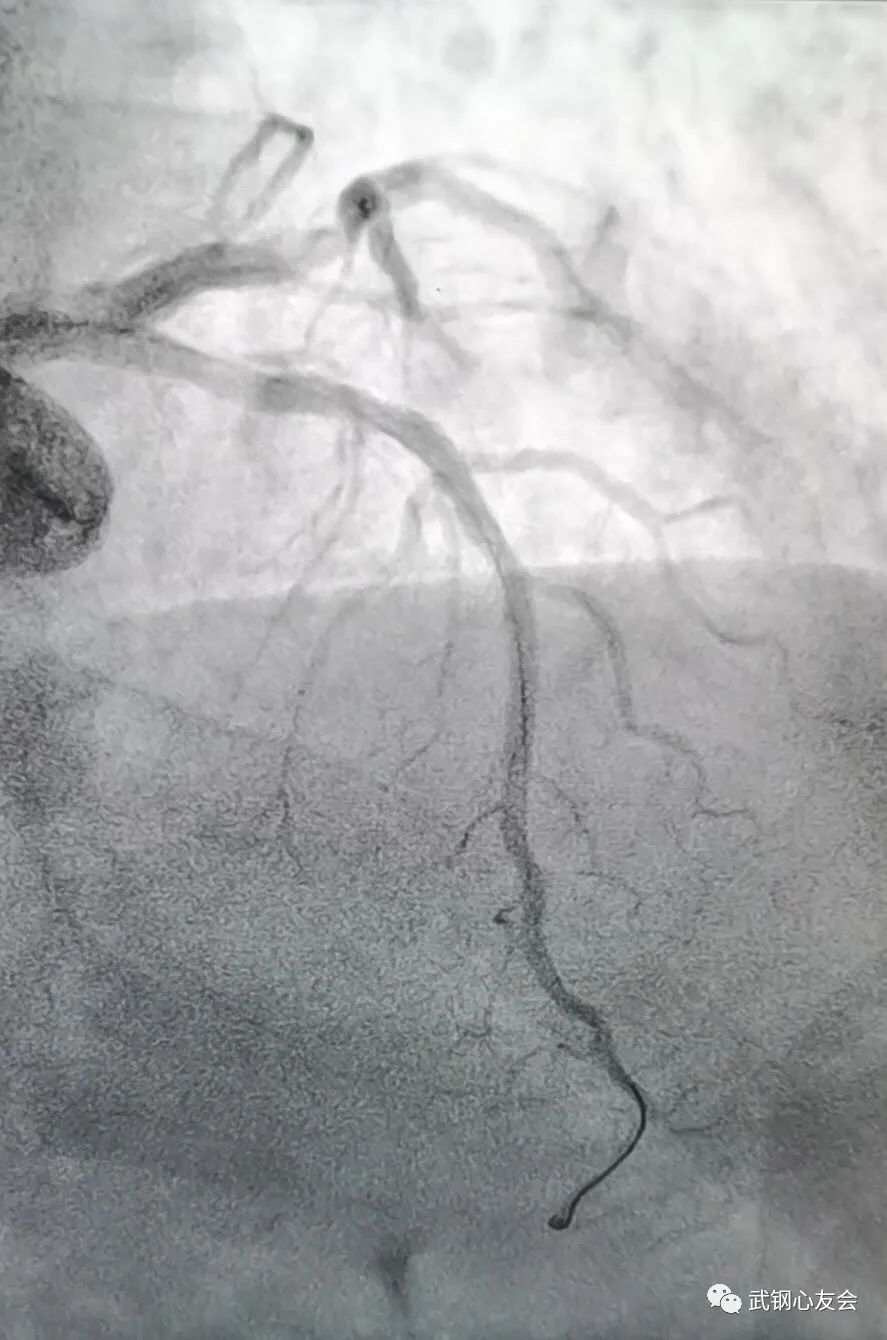

6 月 21 日,由吕学祥主任担任术者,李念主任担任助手为安先生实施了冠状动脉造影术,手术结果显示安先生的冠状动脉前降支中段狭窄了 90%,血管直径及病变部位符合植入生物可降解支架的条件,随后为安先生实施了生物可降解支架植入。术后 3 天安先生恢复良好,未再发作心绞痛,康复出院。